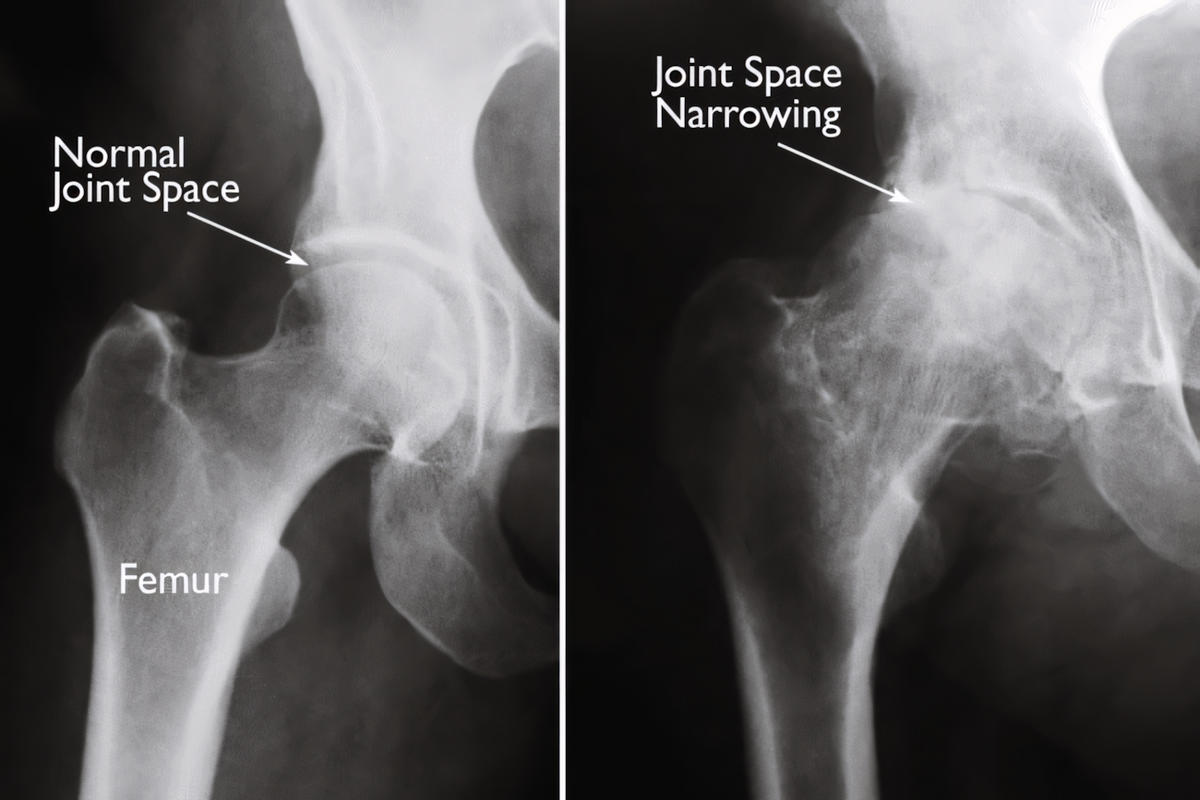

Ακτινογραφία ισχίου αποτελεί την εξέταση πρώτης γραμμής και αναδεικνύει:

Στένωση μεσάρθριου διαστήματος

Οστεόφυτα

Υποχόνδρια σκλήρυνση

Παραμόρφωση κεφαλής